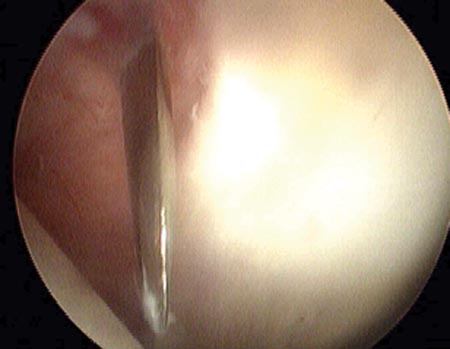

Dentro de las clasificaciones que toman en cuenta la morfología de la lesión mencionamos la enunciada por Lage,18 útil por ser artroscópica, que las divide en (fig. 2, Fig. 3):

Figura 2: Ruptura fibrilar del labrum.